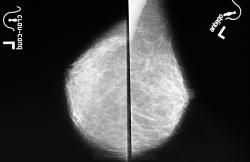

справа округлое образование неоднородное, не высокой плотности - подмышечный л/узел

Скорее всего лимфоузел, т.к.  типичное расположение,  подходит дрожка из сососудов. Учитывая однородную структуру - увеличение свежее, нет признаков склерозорования и замещения жировой тканью, при повторном исследовании должно появиться  замещение жировой тканью-

Сверху два тоненьких сосуда (к сожалению ставить стрелки, как это делают другие не умею), но они идут в разные стороны, что, конечно, не так часто при лимфоузлах но встречается,  контроль необходим.